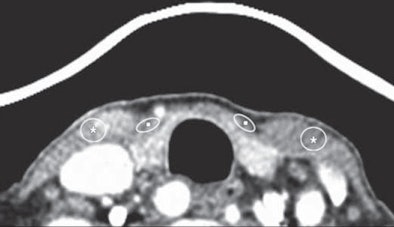

| Compared with unshielded CT image (above), mean attenuations of both superficial neck muscles (strap muscle [squares] and sternocleidomastoid [asterisks]) are higher in shielded image (below), whereas image noises do not show significant difference. Images republished with permission of the American Roentgen Ray Society from AJR 2011; Vol. 196:3, pp. 611-615. |

Lee and his team looked at two groups of patients who were imaged with neck CT but ultimately shown to be without abnormalities. One group had shielding and the other did not. The shields were fabricated from a double layer of bismuth-impregnated latex placed with a 2-cm radiolucent cotton spacer to decrease streak artifacts near the contact surface with the shield. There were no significant demographic differences between the two groups.

The investigators measured CT attenuation and noise in the strap and sternocleidomastoid (SCM) muscles, as well as superficial radiation dose, using a head CT dose phantom containing ionization chambers located at the 3, 6, 9, and 12 o'clock positions.

The results showed that CT attenuation rose with use of the commercial bismuth shield.

"These differences between the shielded and unshielded neck CT examinations were statistically significant (p < 0.01), which implies that the use of the shield resulted in increased CT attenuation of the superficial neck muscles compared with the unshielded CT examination," the authors wrote.

At the same time, noise was unaffected by the use of shielding.

"These differences in noises measured in the superficial neck muscles between shielded and unshielded CT examinations were not statistically significant (p = 0.201 and p = 0.953, respectively)," the study team reported.

However, the shield also produced increased CT attenuation near the shield during neck CT examinations, while image noise was maintained.

"Our results with neck CT image assessment showed that CT attenuation values were inevitably increased in superficial anterior neck muscles below the shielded surface, although a 2-cm cotton spacer successfully prevented an increase in noise associated with shield application," they added.